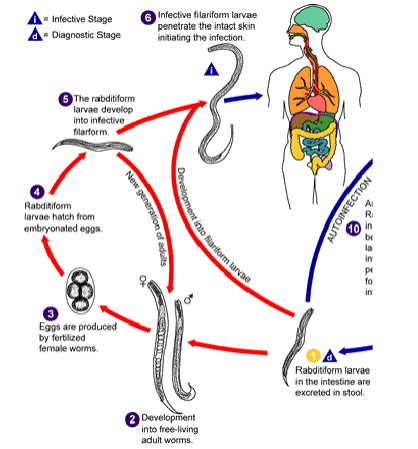

steps of s stercoralis life cycle

infective filariform larvae penetrate skin

autoinfection

filariform enter circulation or lungs where they are swallowed & enter small intestine

become adults in gut; adult female worm creates eggs in intestinal mucosa

eggs hatch into rhabditiform & develop into filariform & restart cycle

free-living

rhabditiform excreted in stool

develop into mature free living worms

worms make eggs & eggs r fertilized → rhabditiform hatch

rhabditiform → filariform → penetrate skin

(strongyloides stercoralis) autoinfection life cycle

Eggs laid in gut hatch into rhabditiform larvae

Mature into filariform larvae

Penetrate intestine, migrate to lung

Asexual reproduction

Only female worms present

(strongyloides stercoralis) free living life cycle

Rhabditiform larvae mature into 4th stage larvae, then adults

Mate, lay eggs, hatch rhabditiform

Larvae mature into filariform larvae that mature into adults

Sexual reproduction

Occurs in temperate climates

(strongyloides stercoralis) parasitic life cycle

Rhabditiform larvae hatch from egg, mature into filariform larvae

Penetrate intact skin of human host

Moves into the auto-infective cycle from there